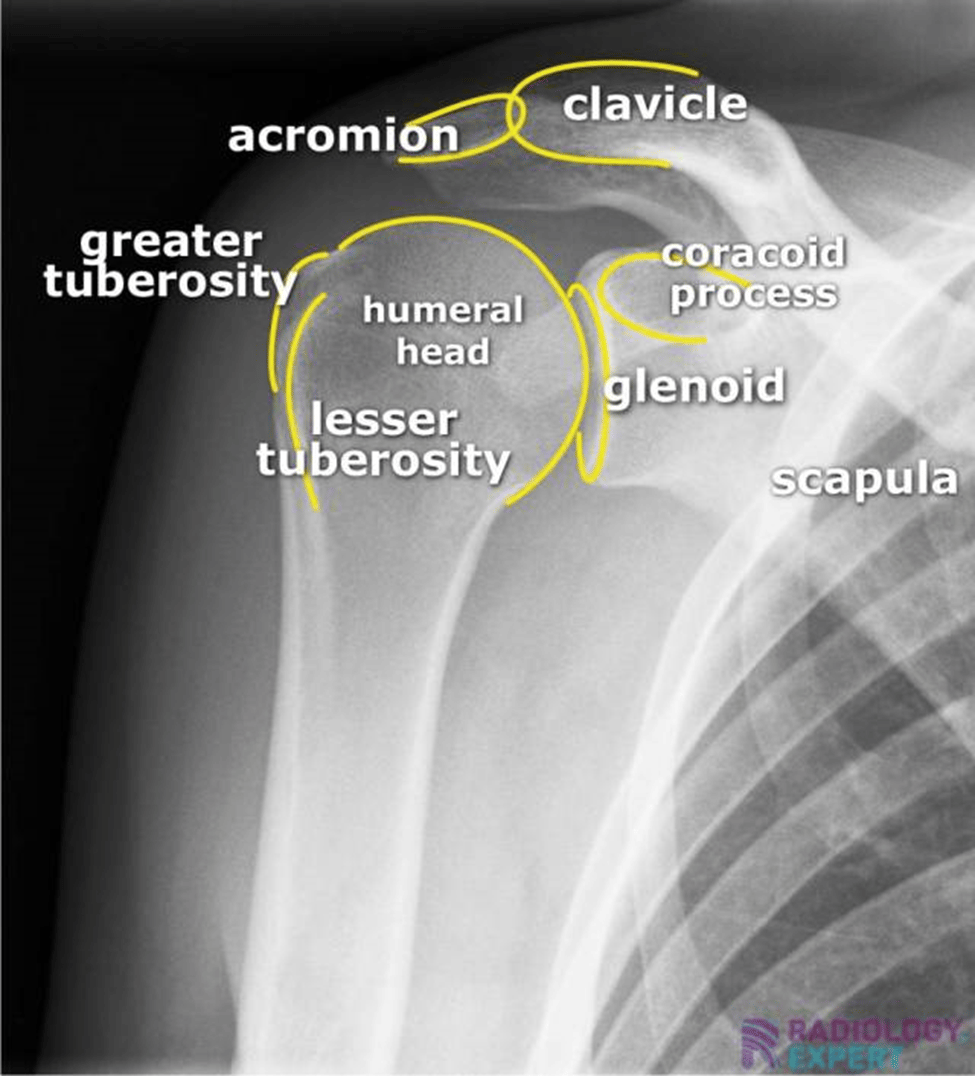

A-P X-Ray of Normal Shoulder

Key Landmarks on Shoulder X-Rays

The Glenohumeral Joint: The Ball and Socket

The round "ball" at the top of your arm bone (humeral head)

The shallow "socket" of your shoulder blade (glenoid)

The space between them should be smooth and even

The Acromion: The “Roof” of Your Shoulder

Appears as a horizontal white line above the ball

Important because that is where many rotator cuff problems occur

The Clavicle: The “Collarbone”

Appears as a long horizontal bone at the top of the x-ray

The ONLY (really, it is) bone that connects your shoulder to your skeleton

The Scapula: The “Shoulder Blade”

Appears as a triangular shape behind the shoulder joint

Contains the socket portion of the joint and the acromion, and acts as an attachment site for ALL of the rotator cuff muscles

What We are Looking For on X-Ray

Narrowing of joint space and/or breaks in the smooth contouring of a joint (for example in arthritis)

Bone spurs or other atypical bony shapes

Obvious breaks or fractures